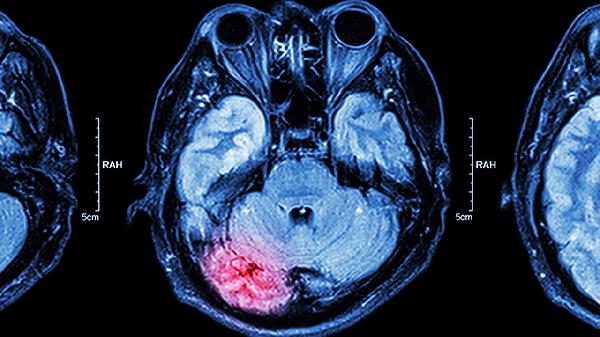

小孩摔到后脑勺需观察是否出现呕吐、嗜睡、意识模糊等症状,判断是否需就医。头部外伤的严重程度可通过意识状态、肢体活动、瞳孔反应、呕吐频率及伤口情况综合评估。

摔倒后1-2次呕吐可能由疼痛刺激引起,但频繁喷射状呕吐伴随头痛,提示颅内压增高。尤其需关注呕吐后是否出现嗜睡加重,此类情况需排除硬膜下血肿等迟发出血。

检查头皮有无肿胀、裂伤或凹陷。较大血肿可能伴有颅骨骨折,小而深的伤口需排除异物残留。清洁伤口时避免按压,出血不止或骨片暴露需专业处理。

受伤后24小时内需保持安静休息,避免剧烈活动或摇晃。睡眠时每2-3小时唤醒一次确认意识状态,可适当冷敷肿胀处但避免直接压迫。饮食选择易消化的粥类、面条,补充富含维生素C的水果如猕猴桃、橙子促进修复。若出现异常哭闹、拒食或发热,应及时复查头颅CT排除迟发性病变。日常建议给婴幼儿佩戴防护帽,家具边角加装防撞条,玩耍时注意看护避免高处坠落。